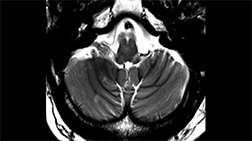

The central vein sign on fluid‑attenuating inversion recovery* (FLAIR*) MRI.